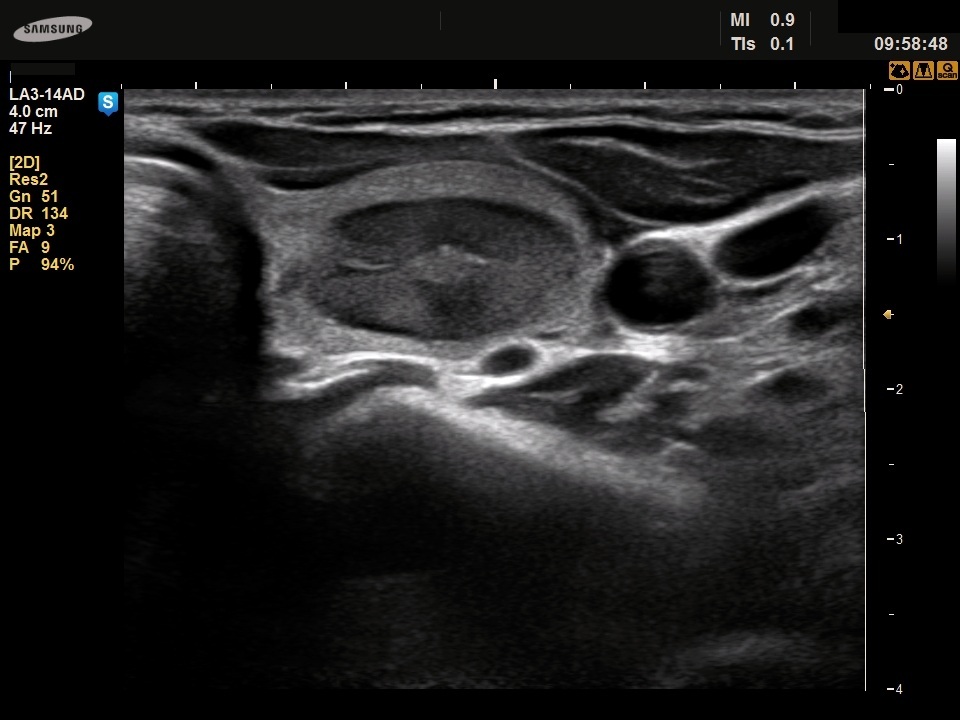

Ethanol sclerotherapy: thyroid cysts - Case 11

Four years after the sclerotherapy (ultrasonographic picture 1)

Left lobe, horizontal scan. Note the presence of a central echonormal area.